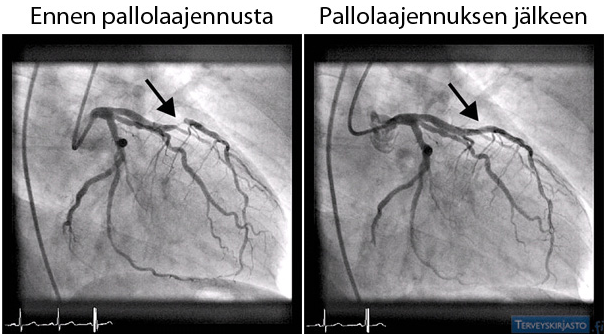

Pallolaajennus avaa sepelvaltimossa olevan tukoksen, jotta veri pääsee virtaamaan normaalisti sydänlihakseen.

Tutkimuksessa sepelvaltimossa olevan ahtauman tai tukoksen läpi pujotetaan kuvauskatetrin kautta ohut lanka. Ahtauman kohdalle viedään pallo, joka puristaa ahtauman suonen seinämää vasten ja avaa sen. Näiden jälkeen ahtaumaan asetetaan yleensä verkkoputki eli stentti, joka estää suonta painumasta kasaan uudestaan.